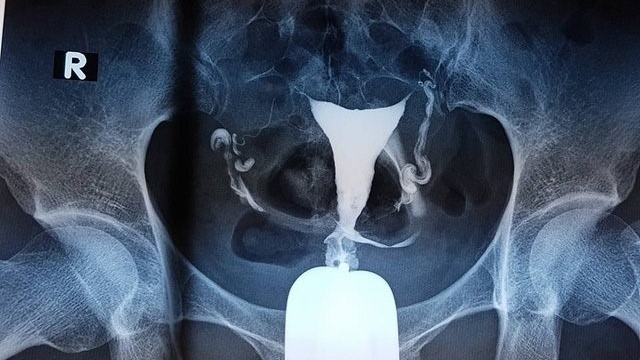

Hysterosalpingography (HSG), hay chụp X-quang tử cung vòi trứng, là một phương pháp dùng để kiểm tra tình trạng bên trong tử cung và vòi trứng. Phương pháp này, bác sĩ sẽ bơm chất cản quang vào tử cung thông qua đường âm đạo và cổ tử cung, sau đó sử dụng tia X-quang để thu thập hình ảnh liên quan đến tử cung và vòi trứng. Tuy nhiên, không phải ai cũng biết cách đọc kết quả chụp tử cung vòi trứng.

Sau khi làm trống bàng quang, bệnh nhân nằm ngửa với chân được đặt cao. Bác sĩ sẽ dùng mỏ vịt để mở âm đạo và quan sát cổ tử cung, sau đó sử dụng một ống nhỏ để đưa chất cản quang vào tử cung. Nếu vòi trứng ở trạng thái bình thường, chất cản quang sẽ đi qua và vào khoang bụng. Ngược lại, nếu vòi trứng bị tắc, chất cản quang sẽ bị chặn lại. Hình ảnh X-quang sẽ được chụp lại và trong một số trường hợp, bệnh nhân có thể cần thay đổi tư thế để thu thập thêm thông tin. Sau khi hoàn thành thủ thuật, bác sĩ sẽ rút mỏ vịt và ống ra ngoài.

Thông qua hình ảnh chụp X-quang tử cung vòi trứng, bạn có thể dễ dàng nhận biết tình trạng tử cung vòi trứng bằng các đặc điểm sau đây:

Kết quả bình thường

Tử cung và vòi trứng có hình dạng bình thường, không có dấu hiệu sẹo hoặc tổn thương. Chất cản quang di chuyển tự do từ tử cung qua vòi trứng và thoát ra ổ bụng một cách tự nhiên. Không phát hiện vật lạ như vòng tránh thai, hoặc khối u hay sự phát triển bất thường trong tử cung.

Trong trường hợp bất thường

Vòi trứng có thể bị sẹo, dị dạng hoặc tắc nghẽn, làm cho chất cản quang không thể di chuyển qua vòi trứng và không thoát ra ổ bụng. Nguyên nhân gây tắc nghẽn có thể bao gồm viêm vùng chậu hoặc lạc nội mạc tử cung, khi mô nội mạc phát triển ở các vị trí bất thường như eo vòi trứng, gây ra tình trạng tắc nghẽn.

Ngoài ra, chất cản quang có thể rò rỉ qua thành tử cung, cho thấy có vết rách hoặc thủng tử cung. Trường hợp tử cung có vách ngăn, tử cung sẽ bị chia thành hai phần bởi lớp mô này.